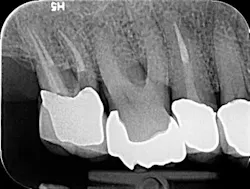

I then employ two instruments—the 30/02 Shaper and the 30/04 Finisher (Tango-Endo, EDS) that are also used in a 30-degree to 45-degree reciprocating handpiece, but designed with a more efficient flute design—to remove tissue and shave dentin away in the longer bucco-lingual isthmuses that may be present. These instruments are also highly resistant to separation, but for caution I suggest limiting their use to three teeth. Generally, there is little need to instrument the canals with larger instruments. If, in fact, the canal is wider than the instrument mesio-distally, in the same way the instruments can broaden the preparation bucco-lingually. It will also accomplish this task in the mesio-distal plane. Once shaped to these dimensions, the canal is properly sealed flooding the canal with epoxy resin cement via a bidirectional spiral applicator and the placement of a single Tango-Endo gutta-percha point (figures 2-3), demonstrated in the before-and-after radiographs.